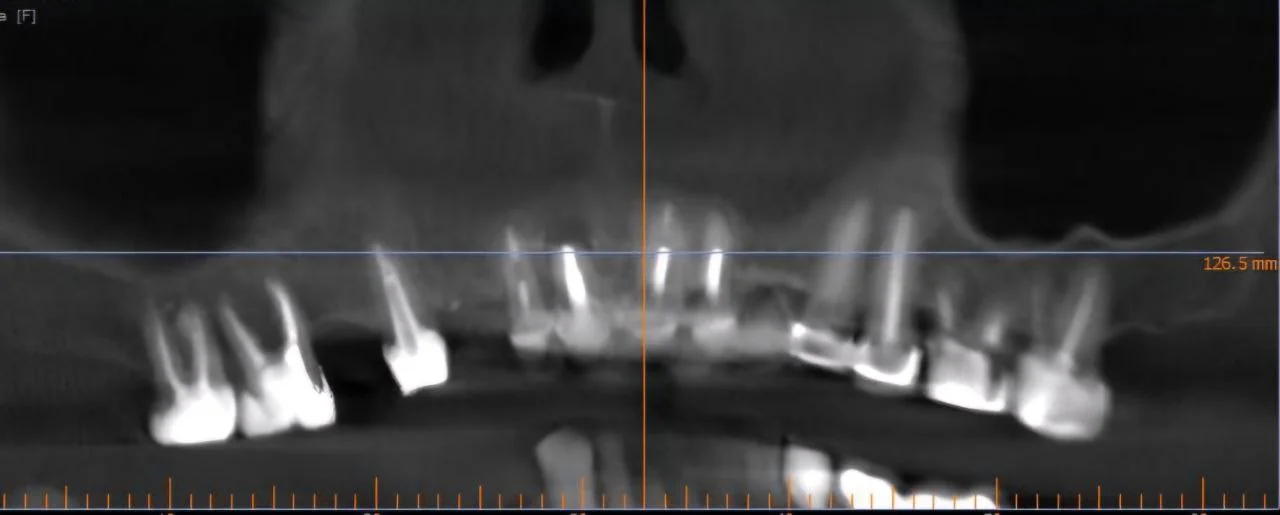

Видалення 4-х зубів, імплантація 4 імплантів Штрауман. Закритий синус-ліфтинг, кісткова пластика.